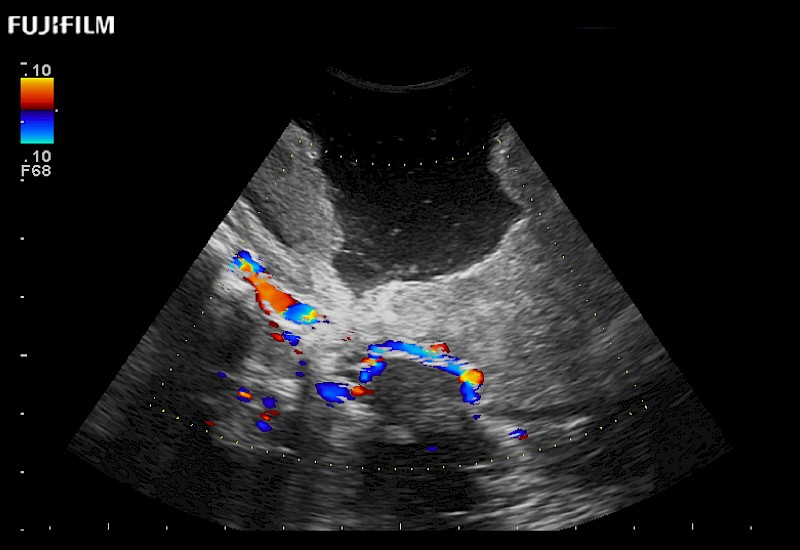

Extraordinary high-resolution digital imaging

Multi-Parametric imaging modalities